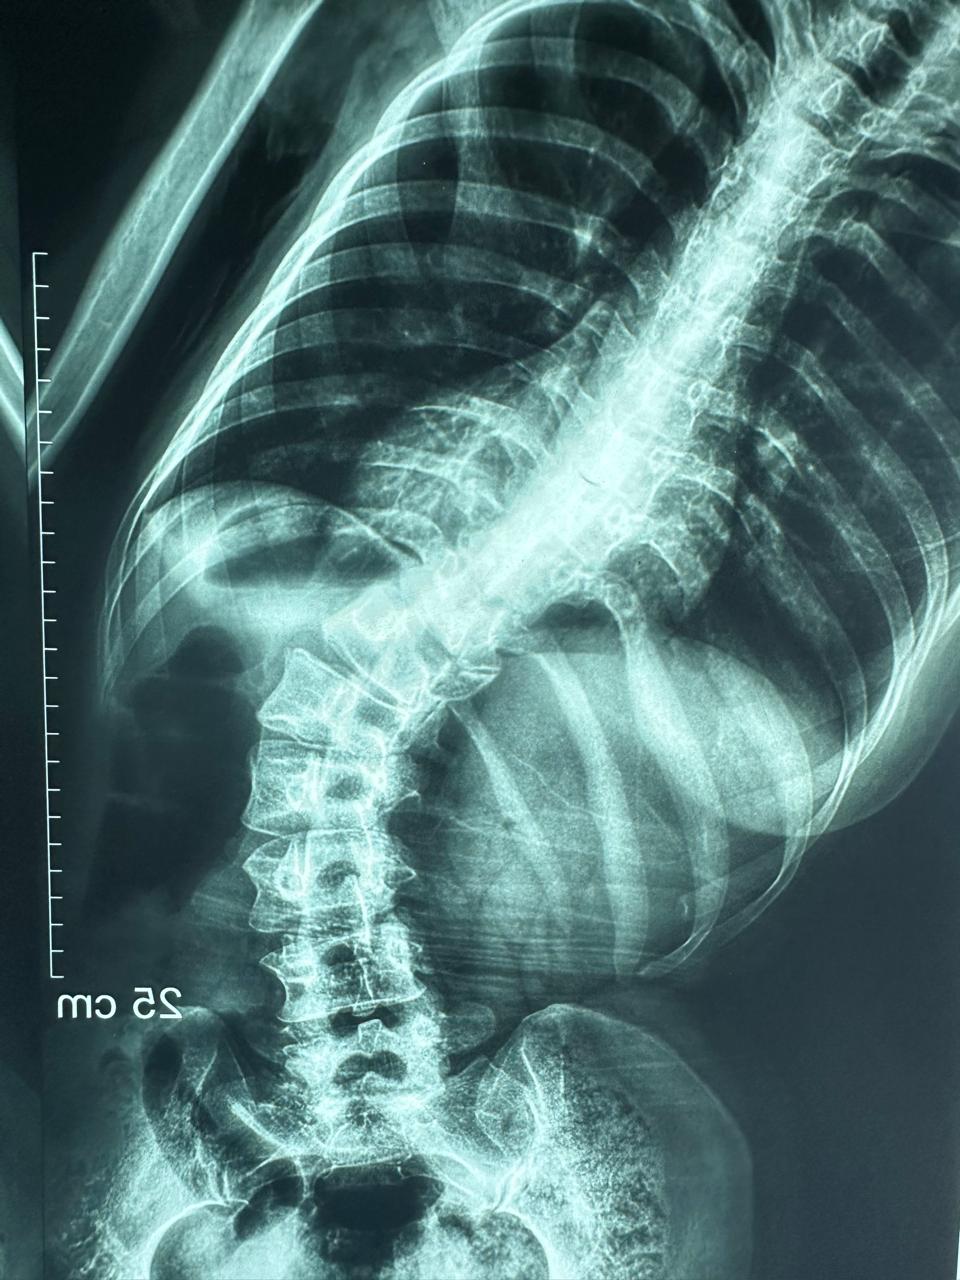

نجح الفريق الطبي بمستشفى قليوب التخصصي في تحقيق إنجاز طبي جديد، وذلك بعد تمكّنه من إجراء عملية دقيقة لمريضة كانت تعاني من اعوجاج شديد بالعمود الفقري، حيث تم إصلاح وتشريح الاعوجاج وتثبيت الفقرات باستخدام 20 مسمارًا معدنيًا لضمان ثبات واستقامة العمود الفقري.